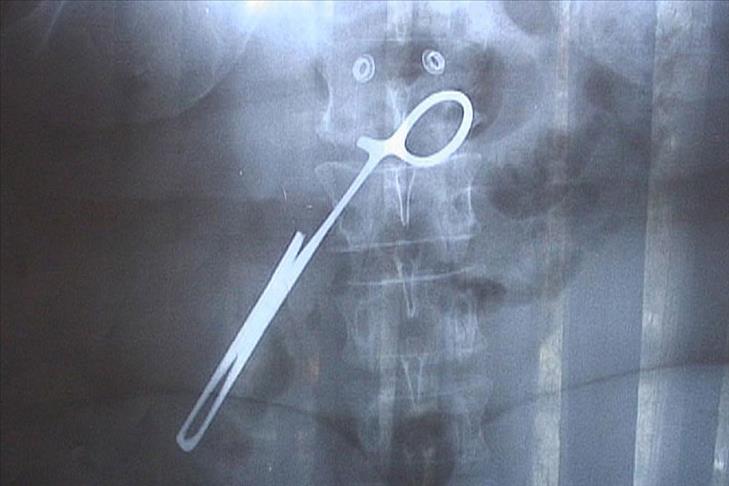

Bulun'a göre sıklıkla karşılaşılan hataların başında yanlış bölgenin ameliyat edilmesi, vücutta yabancı cisim bırakılması, enfeksiyon, ilaç, kan ve anestezi hataları geliyor.